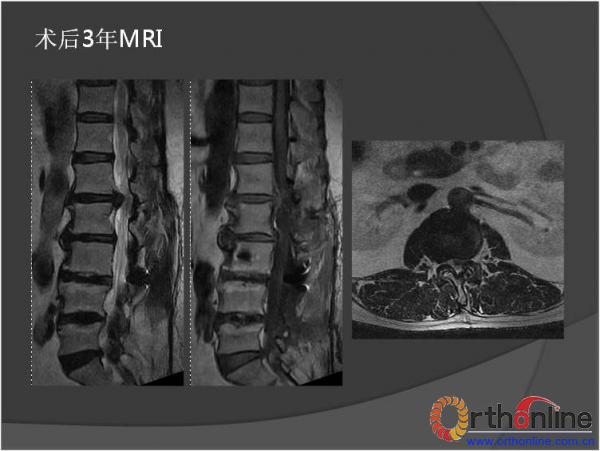

北京军区总医院骨科李放教授报告了一例腰椎管狭窄脊柱融合术后、退变侧凸加重并出现邻近节段退变病、而后进行翻修的病例。患者男性,64岁,2009年因腰椎管狭窄症行椎板减压,L3-4、L4-5PLIF手术,术后3年间疗效满意,后由轻度扭伤后再度出现腰痛及下肢疼痛,经检查后发现L2-3间盘退变、L1-2间盘突出并出现退变性腰椎侧凸,于2013年2月行翻修手术后痊愈。